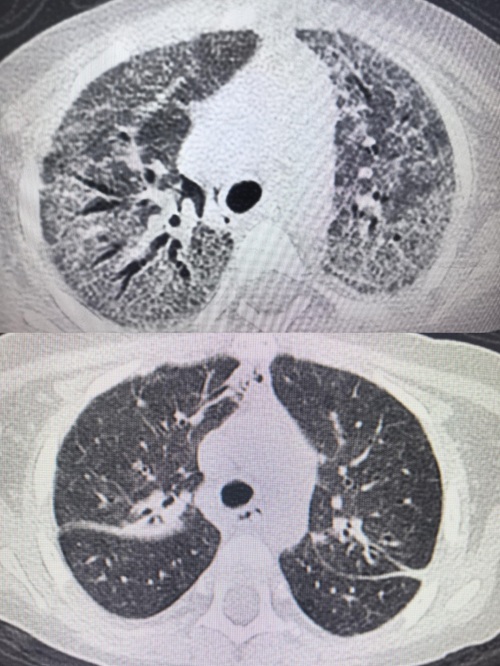

2025年12月10日,小佩因发热2天、气促半天被收治入院。该患儿一年前确诊急性淋巴细胞白血病,此次在维持化疗阶段发生肺部耶氏肺孢子菌感染,病情迅速进展为重度急性呼吸窘迫综合征并继发呼吸衰竭,后进一步发展为肺纤维化。入院时,小佩表现为呼吸急促、精神萎靡、尿量减少及经皮血氧饱和度持续下降,生命体征不稳。

PICU团队接诊后立即启动应急救治流程。在给予呼吸支持、抗感染治疗及纤维支气管镜检查与肺泡灌洗后,患儿氧合状态一度维持稳定。12月11日凌晨,其血氧饱和度再次下降,无创呼吸机辅助通气难以维持,医护团队果断行气管插管,转为有创呼吸机辅助通气。由于呼吸机参数持续处于高位,科室随即组织多学科专家会诊,制定并实施“个体化综合救治方案”,涵盖呼吸功能支持、肺康复治疗、抗感染管理、营养干预及皮肤与口腔护理等多个方面。针对肺部感染及纤维化,救治团队先后实施五次纤维支气管镜下肺泡灌洗术及其他最新治疗措施,并根据病情动态调整抗感染方案。在60天救治过程中,小佩的呼吸支持方式经历了从无创通气、气管插管、气管切开,最终降至鼻导管吸氧的逐步过渡,肺功能逐步恢复。